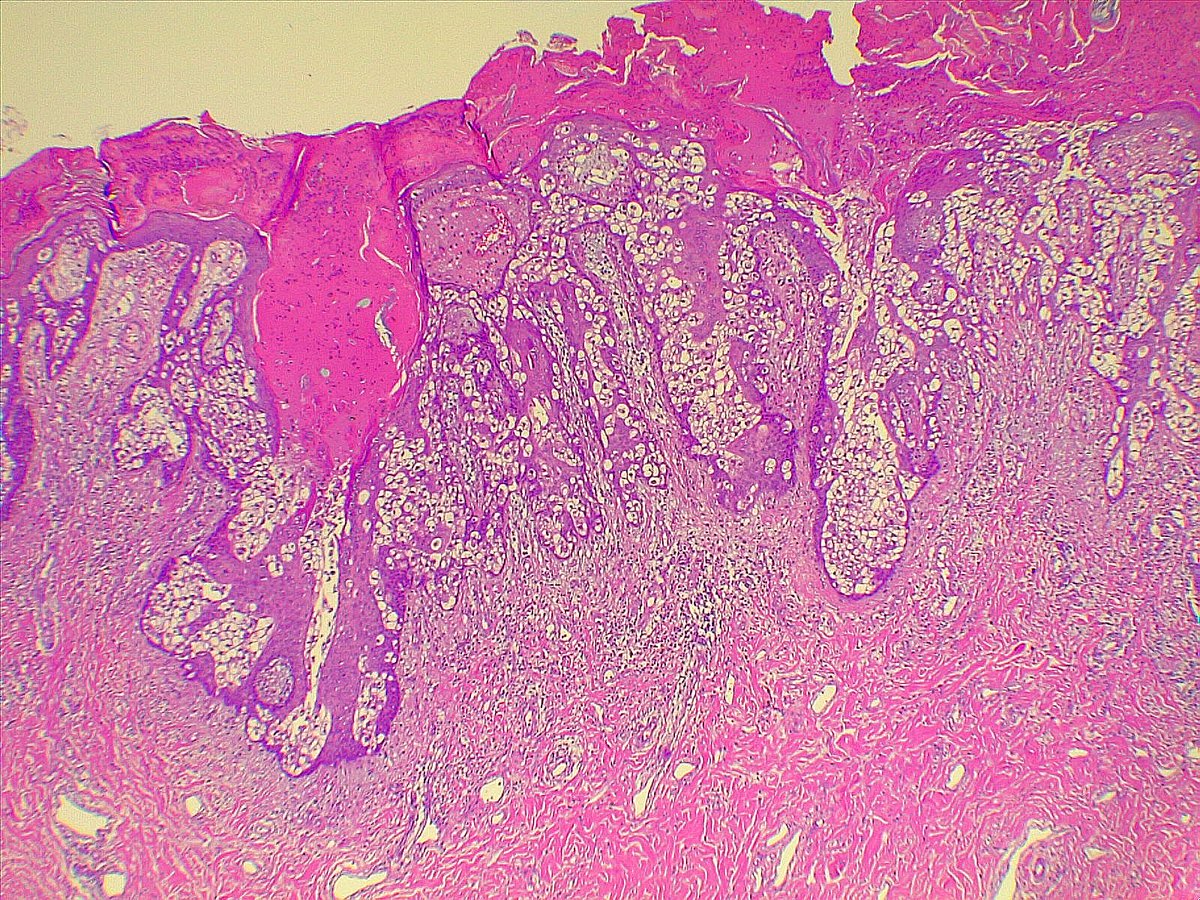

The moment high grade DCIS becomes an invasive carcinoma floating in mucin! #breastpath #pathx #PathTwitter

🔍 This figure serves as a reminder that microinvasion is focal. In high-grade DCIS especially, examine every slide—including ER/PR—to ensure focal invasion isn't overlooked. Arch of Path & Lab Med 148, 1; 10.5858/arpa.2022-0467-RA #Pathology #Breastpath #PathX #PathTwitter